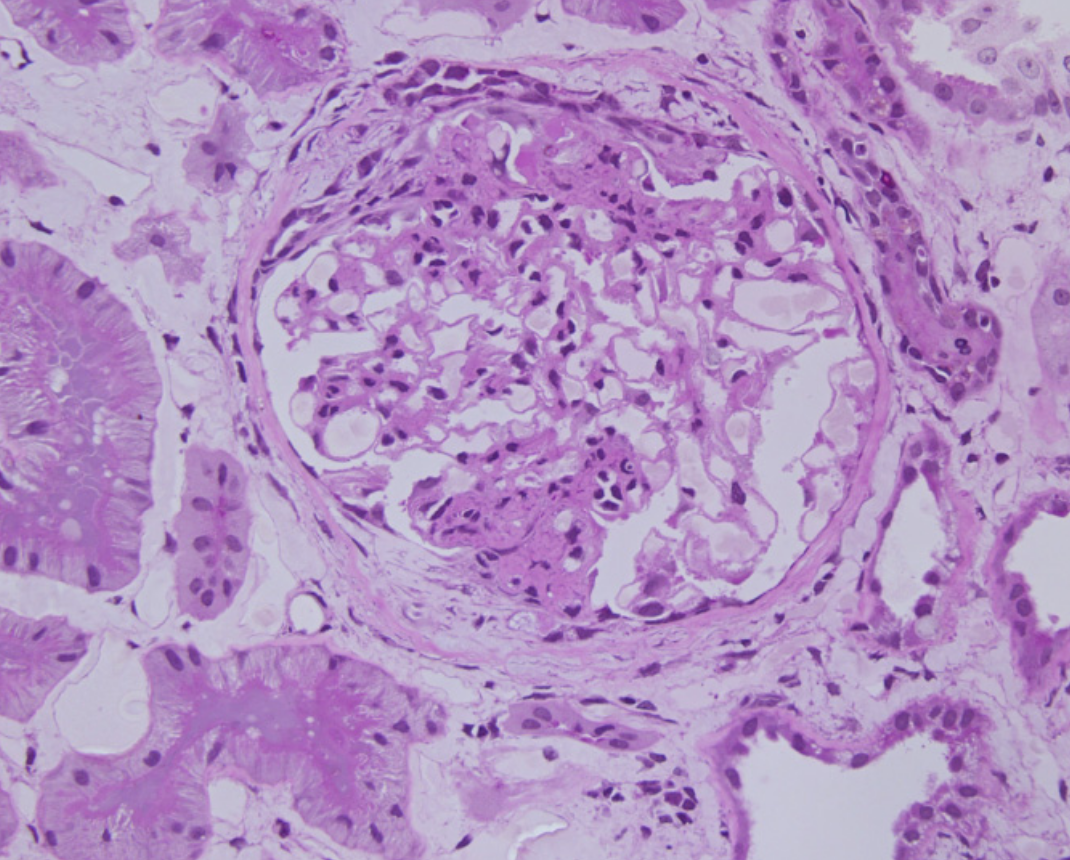

Hypercellularité endocapillaire

Augmentation du nombre de cellules dans la lumière capillaire entrainant un rétrécissement de la celle-ci.